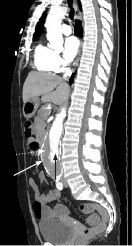

Ultrasound is the modality of choice for detection and screening; however, computed tomography (CT) angiography of the abdomen is helpful to better characterize the anatomical location and aneurysm characteristics, predict prognosis, and can aid in surgical planning. (See Figures 1 and 2.) Understanding the exact location of the aneurysm in relationship to the renal arteries and other vascular structures can help with repair approach and feasibility. For example, aneurysms with shorter necks have poorer outcomes. In stable patients, it also can help identify impending rupture and the extent of aortic wall involvement. It should be noted that unstable patients should not be sent to the CT scanner prior to stabilization.18

Figure 2. Computed Tomography Showing Abdominal Aortic Aneurysm with Intramural Thrombus, Sagittal Plane View |

White arrow: aortic wall; black arrow: aortic lumen; white dotted arrow: thrombus Source: Image courtesy of J. Stephan Stapczynski, MD. |